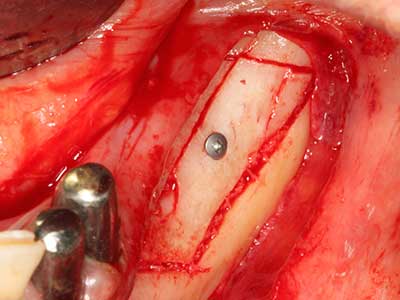

Когато се извършват хирургични процедури върху кост в непосредствена близост до чувствителни структури като кръвоносни съдове или нерви, ротиращите инструменти създават значителен риск за ятрогенно нараняване. Пиезоелектрическите апарати могат да бъдат от помощ при препарация на костно покритие и отстраняване на твърда кост близо до нерви, особено за оголване на нервите след ятрогенно нараняване, както и по време на латерализация на нервите за резекционни и реконструктивни процедури или поставяне на имплант (Фиг. 17-20). Лекият контакт между пиезонакрайника и нерва по принцип не води до нараняване, но ако действате непредпазливо с трионообразни движения или приставки за остатъчен костен субстрат, може да причините временно или перманентно увреждане на нерва. Въпреки това, рискът от увреждане се счита за много по-малък, отколкото при употреба на триони или ротиращи инструменти (Pereira, Gealh et al. 2014).